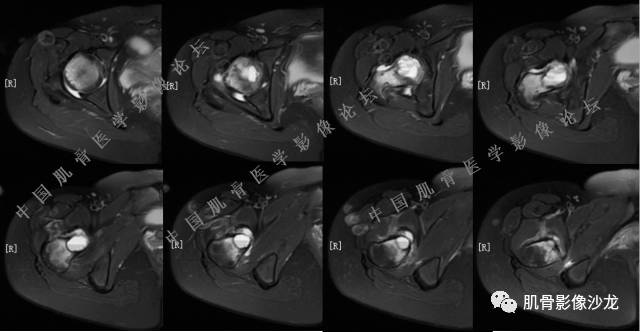

主诉:右大腿疼痛、活动受限20天

现病史:患者于20天前无明显诱因出现右下肢疼痛,活动受限,疼痛呈阵发性,活动后加重。自行口服止痛药芬必得,效果不佳,至当地医院治疗,检查发现右侧股骨近端病变。遂来诊

葛英霖 20:30 原发或继发动脉瘤样骨囊肿,继发于巨细胞瘤,软骨母,纤维组织细胞瘤,骨母等等

向以四 20:30 软骨母合并ABC,

医影在线 20:30 软骨母,/继发ABC

飞鹰行动 20:31 T2信号高,有软骨成分

Echo 20:32 T2确实有一块区域很亮 ,并有野液平

飞鹰行动 20:35 骨皮质破坏,周围骨质异常信号

葛英霖 20:36 这不是良性病变

葛英霖 20:36 中间型可能性极大

葛英霖 20:37 明显侵蚀骨内膜啊,硬化边也不完整 (细箭头所示)

葛英霖 20:43 提不提也很明显继发了abc

葛英霖 20:44 是

葛英霖 20:46 明显的多囊状改变,液液平面